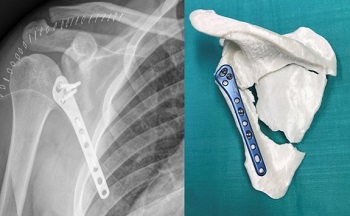

En esta ocasión, se trata de una fractura de escápula en la que se ha aplicado la tecnología de Impresión 3D para su tratamiento por parte del Dr. Fernando García de Lucas y su equipo de Cirugía Ortopédica y Traumatología del hospital FREMAP de Majadahonda.

Gracias a esta técnica e inicialmente sobre la impresión de 3D a escala real, se llevó a cabo la reducción de la fractura y la fijación interna, con la misma placa con la que se realizó el tratamiento definitivo.